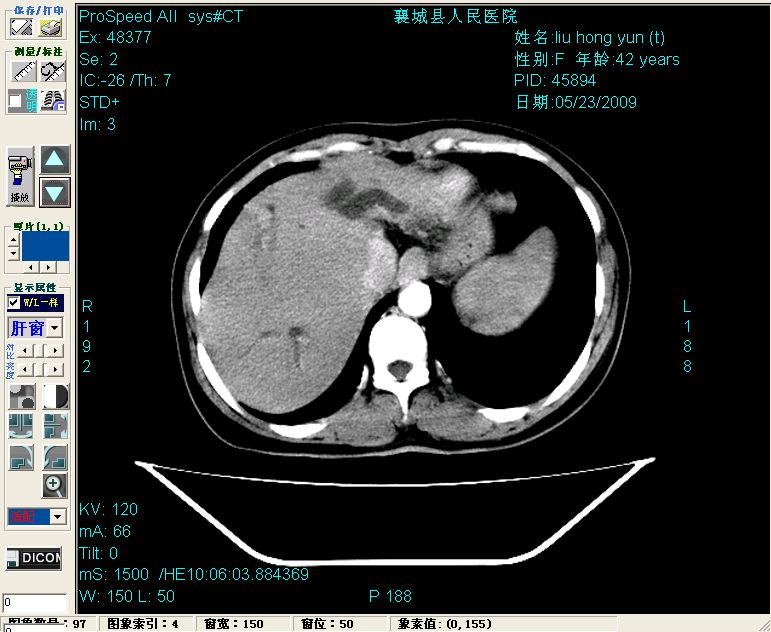

平扫:

平扫左肝外叶体积显著减小,左肝外叶见多房囊性低密度区,左肝实质及右肝前叶浅表实质呈低密度改变,左肝及右肝前叶胆管扩张,脾大